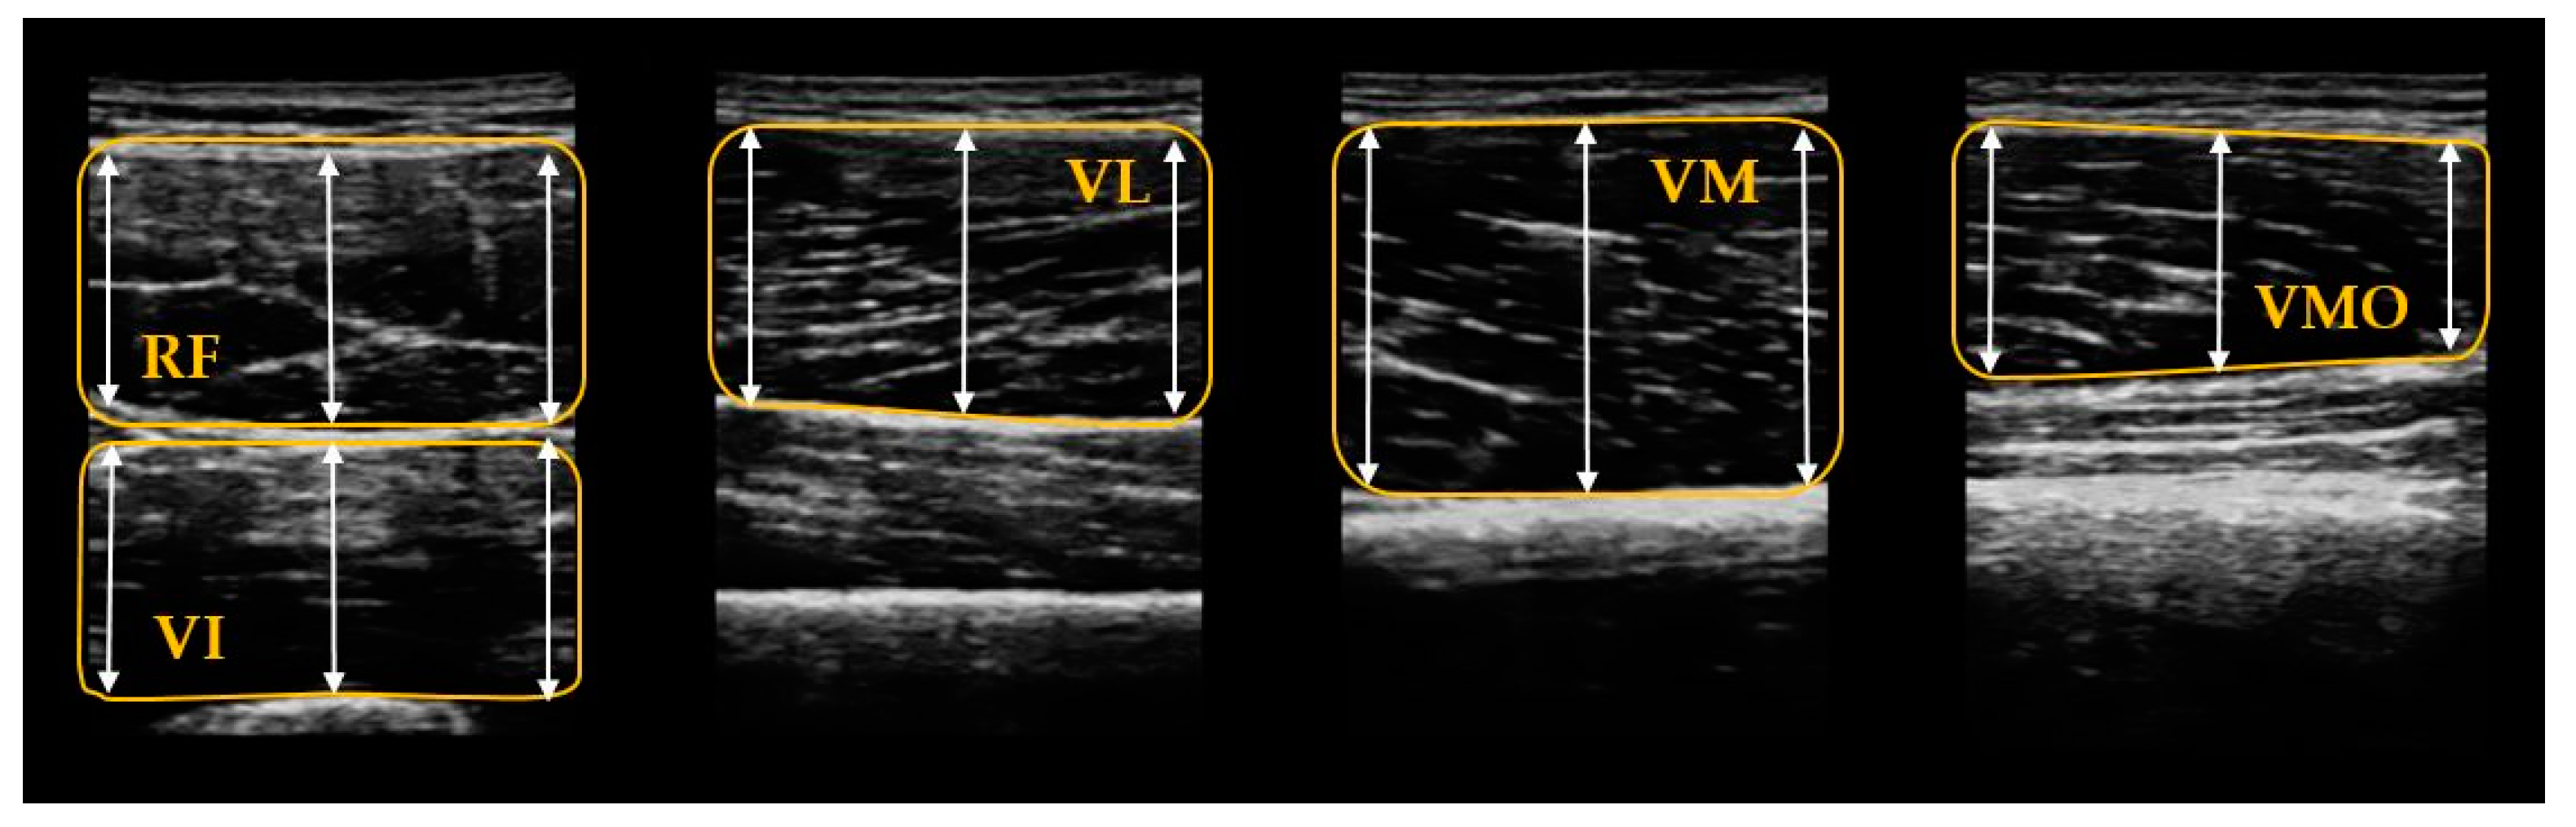

2.3.1. Muscular Thickness Measurement

2.3.5. Ultrasound Image Analysis